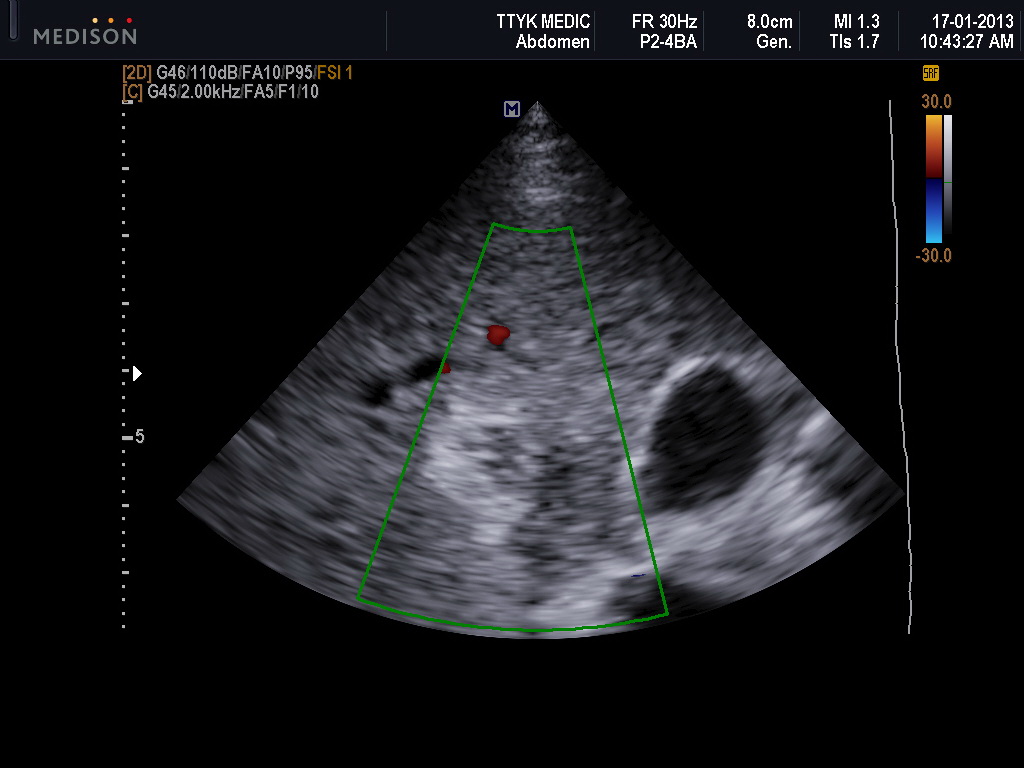

Bệnh nhân nữ 30 tuổi, PARA 1011, tiền sử mổ TNTC ở vòi tử cung bên phải; kinh nguyệt đều, vòng kinh 30 ngày. Bệnh nhân bị chậm kinh một tháng, đau âm ỉ hạ sườn phải 1 tháng, không ra máu âm đạo. Bệnh viện Phụ Sản Hà Nội nghi u nguyên bào nuôi và chuyển đến Bệnh viện Phụ Sản Trung ương. Xét nghiệm β-hCG: 73.047 IU/L; siêu âm Doppler: dưới gan có hình ảnh túi thai d=35mm, chiều dài phôi: 22mm, tim thai (+). Chẩn đoán thai dưới gan. Nội soi: khối thai 3cm nằm ở cạnh phải túi mật, gần tĩnh mạch cửa. Bóc khối thai và cầm máu bằng dao điện và chèn Spongel. Xét nghiệm β-hCG sau 72 giờ: 14.109 IU/L. Giải phẫu bệnh: gai nhau điển hình.

| Hình 3. Hình ảnh siêu âm của bệnh án 2 |